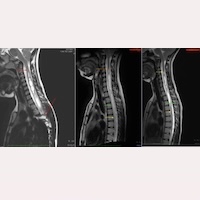

A evolução favorável de um caso com Síndrome de Arnold-Chiari I e Siringomielia Idiopática, aos 7 anos após a aplicação do Filum System® Ler mais » 04 Julho, 2025